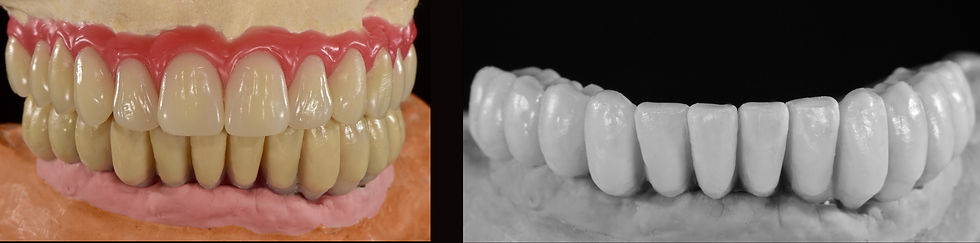

Finalizzation of the upper overdenture and the lower Toronto Bridge in cobalt chrome and molded composite

Delivery of both final prosthesis

Case study in the articulator for the assembly of the definitive mandibular Toronto Bridge and the new removable upper prosthesis

Upper overdenture: mounting elements with wax